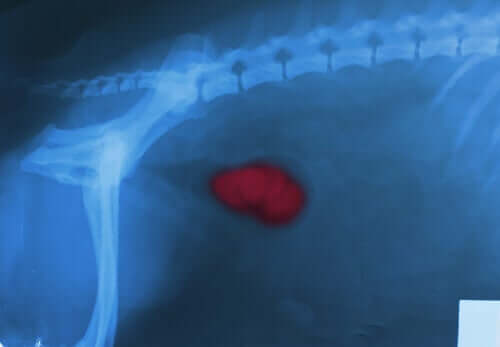

Le développement de calculs rénaux est dû à un excès de certaines substances, un excès que les reins ne parviennent pas à expulser. Ces substances s’accumulent alors et forment des cristaux. Ces substances peuvent être le calcium, l’oxalate ou encore l’acide urique.

Les calculs rénaux peuvent rester dans n’importe quelle partie du système urinaire, des reins jusqu’à la vessie, et endommager la paroi interne. C’est ce qui provoque le saignement.